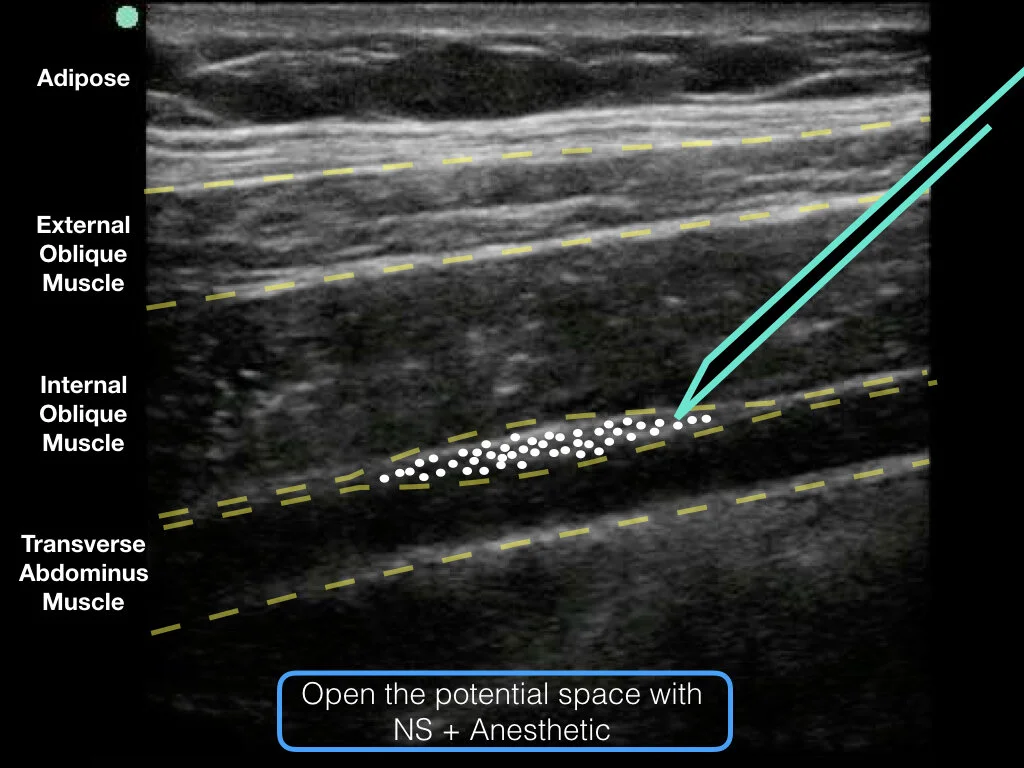

TAP Block - Transverse Abdominus Plane Block

Transverse Abdominal Plane Block

Indications - abdominal wall abscess drainage, appendicitis, epiploic appendagitis, etc.

The nerves run from the spinal canal and lay on top of the transverse abdominus muscle.

All 3 muscle planes will be visualized if you are on the lateral abdominal wall.

The goal is to deposit fluid + anesthetic in the fascial plane above the TAP muscle.